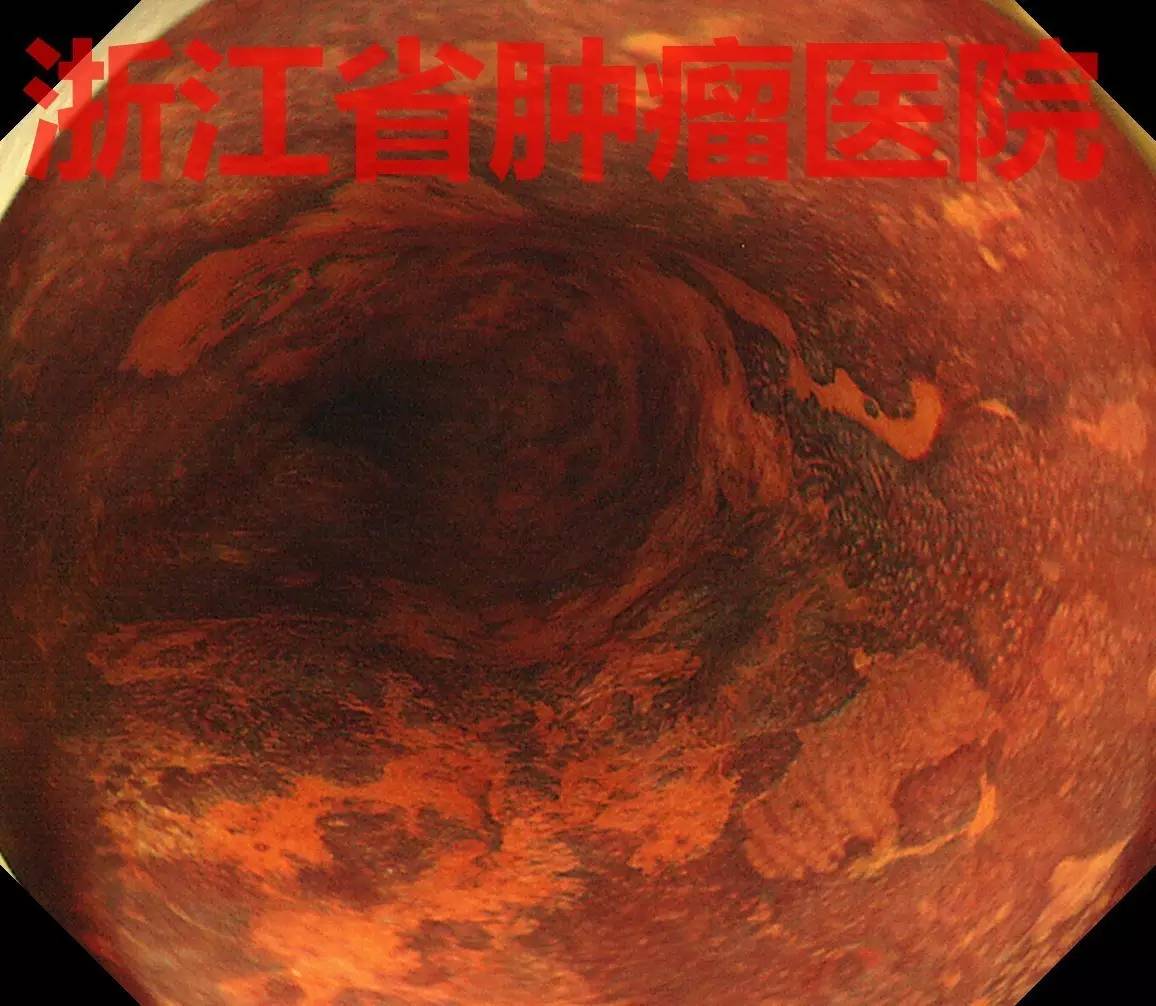

食管中段距门齿25-30 cm约3/4周黏膜粗糙充血,边界不清,表面见有异常白色角化物质附着,局部有黏膜缺损表现。

NBI弱放大可见病变管壁近全周见棕褐色,几乎没有正常背景。表面有多发白色物质附着。